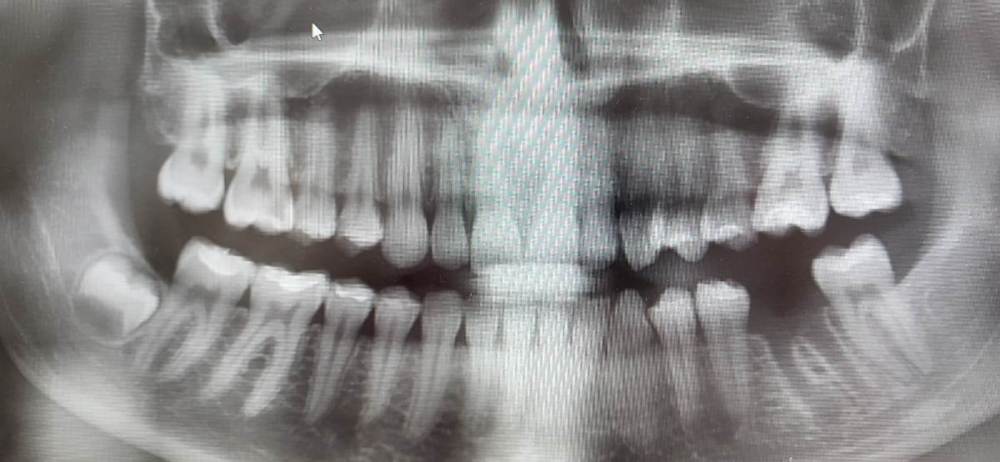

Irouil Опубликовано 19 марта, 2024 Автор Поделиться Опубликовано 19 марта, 2024 Подниму тему Мы тут как-то обсуждали трансплантацию зубов с несформированными верхушками с целью сохранения их витальности А с какого срока можно забирать зачаток под трансплантацию? Понятно, что должно быть сформировано ЦЭС + какая-то часть корня чтобы обеспечить его стабильность. А есть ли какие-то конкретные рекомендации по данному вопросу? Есть вот такая пациентка 18 лет, планирую ждать пока зачаток созреет до пересадки, но долго её мариновать тоже не хочу Ссылка на комментарий

АнтонТЛТ Опубликовано 19 марта, 2024 Поделиться Опубликовано 19 марта, 2024 Цукибоши читал же? Я скидывал его статью из книжки, там как раз на рентгенах показано на сколько должен быть сформирован зачаток 1 Ссылка на комментарий